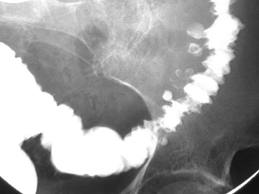

Cuando no existe inflamación de algún divertículo, muchas veces los pacientes se encuentran asintomáticos, o presentan síntomas vagos como dolor mal definido en la parte central del abdomen o en el cuadrante inferior izquierdo, distensión flatulenta y ligera alteración del hábito intestinal. Y una radiografía con medio de contraste puede mostrar la enfermedad.

También se puede demostrar la Diverticulosis mediante una colonoscopía

Si el paciente se presenta con signos abdominales de peritonitis, con o sin síntomas signos de una infección importante, la necesidad de laparotomía es obvia. La presencia de aire libre en cavidad en la cavidad peritoneal es una indicación absoluta para cirugía, pero solo el 70% de los pacientes demuestran aire libre, cuando hay perforación. Algunos pacientes se presentan con signos de inflamación abdominal que requieren observación estrecha; en estos pacientes, la continuación de evidencias locales y sistémicas de sepsis obligan a la laparotomía. Un enema evacuante puede ser de ayuda para demostrar la extravasación en el colon sigmoides.